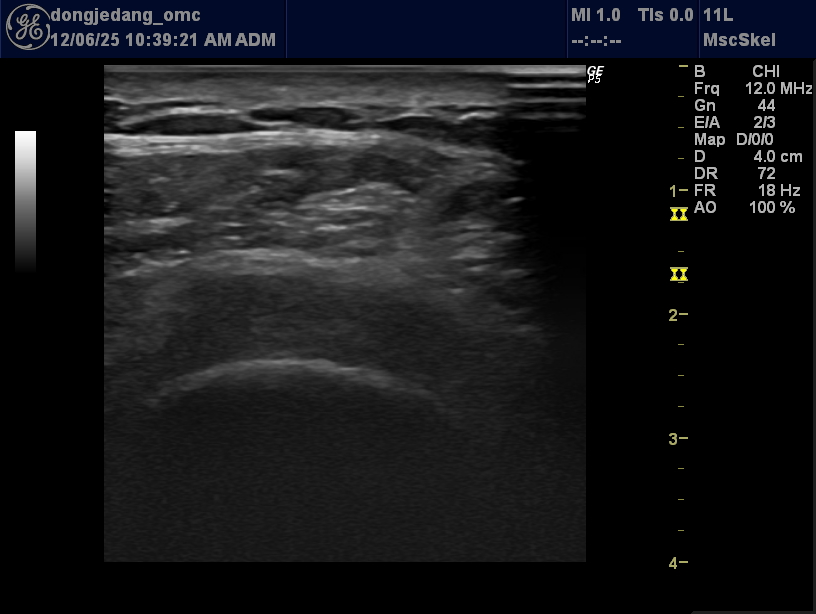

초음파 이미지

• 대퇴골 관절면의 경미한 피질 불규칙성(Cortical irregularity) 초자연골(Hyaline cartilage) 두께의 전반적 보존 및 국소적 경계면 모호 뚜렷한 거대 골극(Osteophyte) 형성이나 연골하 낭종(Subchondral cyst) 부재 관절강 내 유의미한 삼출액(Joint effusion) 저류 관찰되지 않음 우슬 초기 퇴행성 관절염(Early Degenerative Osteoarthritis) 소견 임상적 중증도 분류(Kellgren-Lawrence Grade) 추정 시 Grade 1 (미세한 골극 형성 가능성 및 관절 간격의 변화가 의심되나 확정적이지 않은 상태)에 해당할 가능성이 높음. 46세 남성임을 고려할 때 연령 증가에 따른 자연스러운 초기 변화와 병적 변화의 경계선상에 있는 것으로 사료됨.